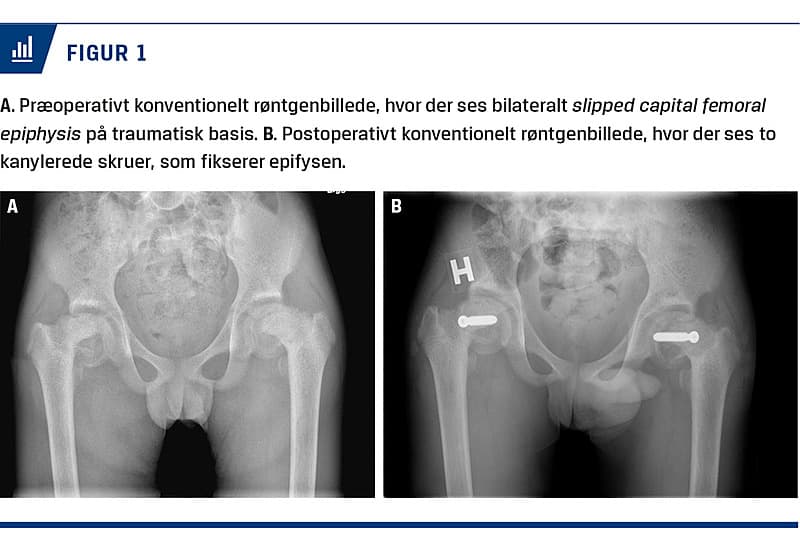

Ved den kliniske undersøgelse lokaliseredes der smerter i hoften. En røntgenundersøgelse viste bilateral SCFE, som syntes at være af ældre dato (Figur 1A). Differentialdiagnostisk overvejede man nontraumatisk SCFE, men da patienten ikke havde de klassiske disponerende faktorer, og der var sammenfald med de epileptiske anfald, vurderede man, at traumatisk SCFE pga. epileptiske anfald var den mest sandsynlige diagnose.

Patienten blev behandlet med plasterstræk og opereret dagen efter, hvor caput femoris skruefikseredes in situ med to kanylerede skruer (Figur 1B). Efter seks uger uden støtte observeredes uændret stilling af epifyserne på røntgenbillederne, og patienten påbegyndte mobilisering med fuld støtte.